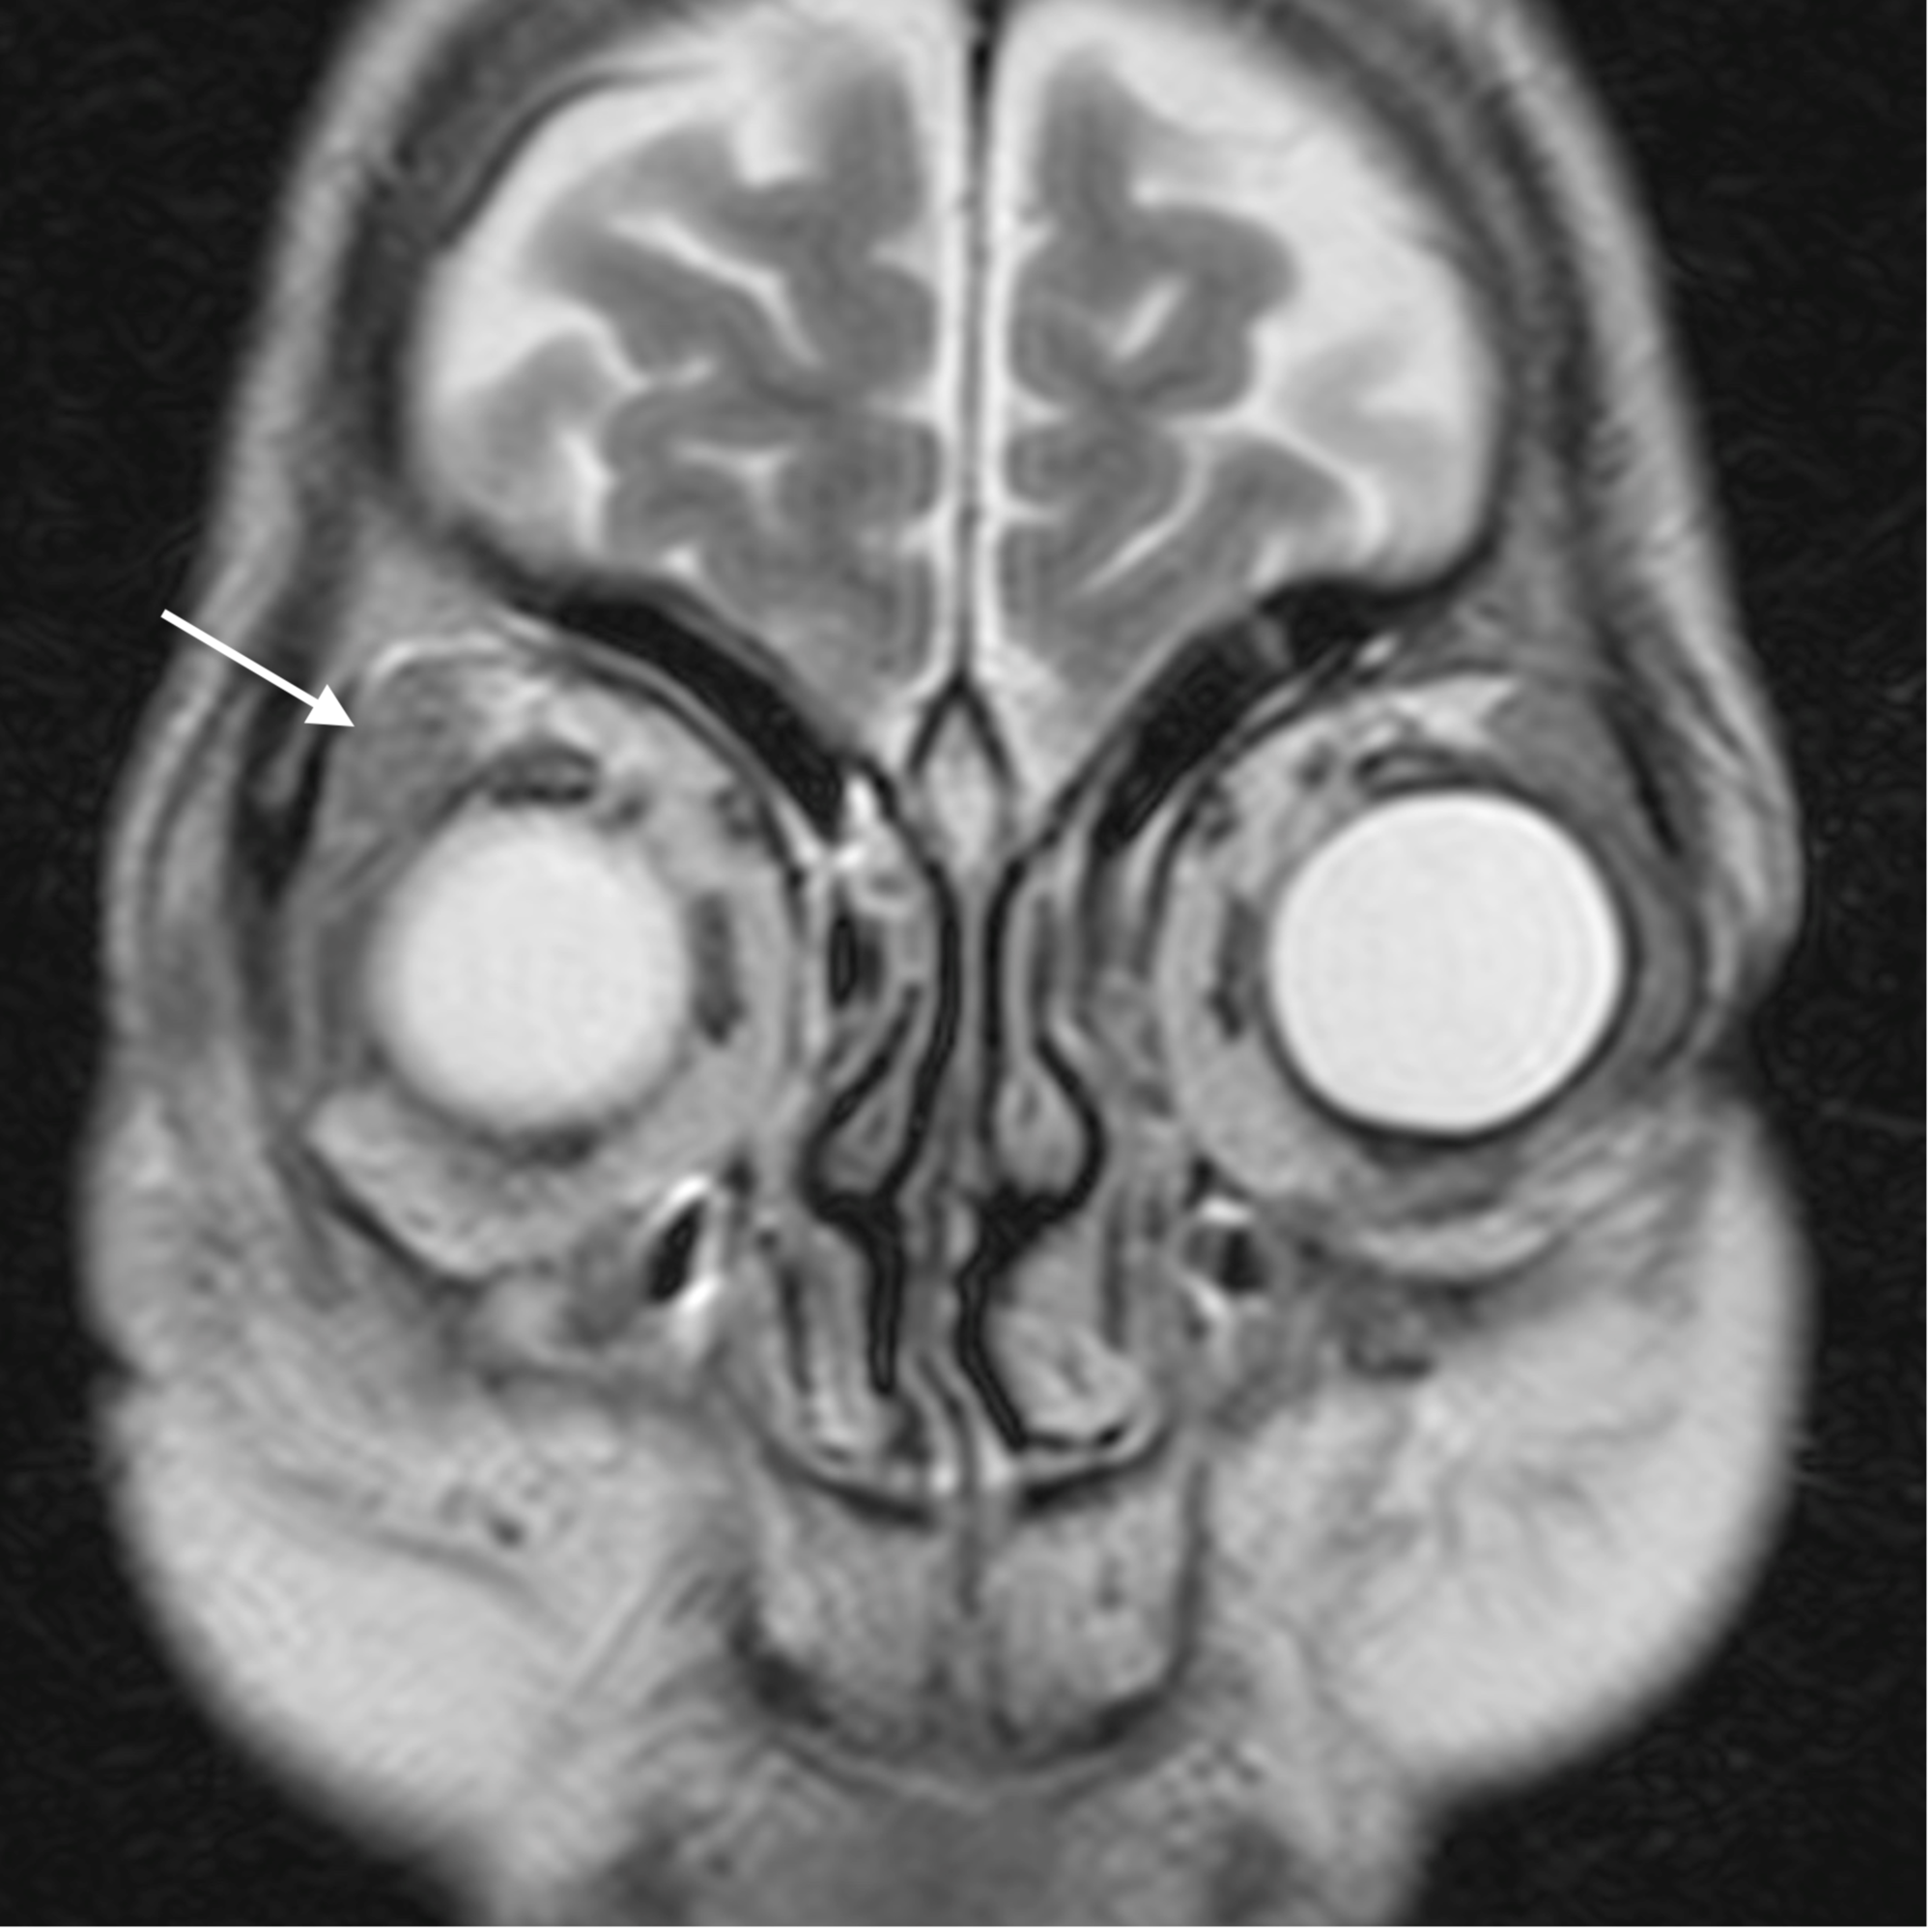

Orbital cellulitis causes diffuse, oedematous infiltration of the orbital connective tissue that is best demonstrated by the high signal intensity in T2-weighted fat-saturated sequences. Other findings are swelling and ill-defined margins of the extraocular muscles and exophthalmos [2]. Orbital cellulitis may be complicated by an abscess, which may form in the extraconal or intraconal orbit separate from the bone [3].

Contrast administration is imperative to distinguish an abscess from a phlegmon and edema. The center of the abscess shows restriction of diffusion on diffusion-weighted imaging (DWI) and demonstration of this finding may obviate the need for intravenous contrast administration in patients who have a contraindication to contrast especially the diabetics who commonly have associated nephropathy. MRI has a high sensitivity in the detection of cavernous sinus thrombosis, which is an uncommon but serious complication of orbital cellulitis and paranasal sinusitis. T2W fat-suppressed sequence is especially useful for the detection of edema related to orbital infections. Poor bony detail, susceptibility to artifacts, lack of wider availability, and higher costs remain disadvantages of MRI.

The main complications of orbital cellulitis (Figures 2-4) encountered in our study were:

1. An orbital abscess (Figures 5-6);

2. Preseptal cellulitis and abscess (Figures 7-8);

3. Periorbital cellulitis (Figures 9-10);

4. Dacryoadenitis (Figures 11-12);

5. Optic neuritis/perineuritis (Figure 13);

6. Cavernous sinus thrombophlebitis and thrombosis (Figure 14).

The most common complication of orbital cellulitis was orbital/periorbital abscess formation (eight cases, 53.3%), followed by optic neuritis (four cases, 26.67%), intracranial involvement (four cases, 26.67%), dacryoadenitis (three cases, 20%) and cavernous sinus thrombophlebitis (three cases, 20%).